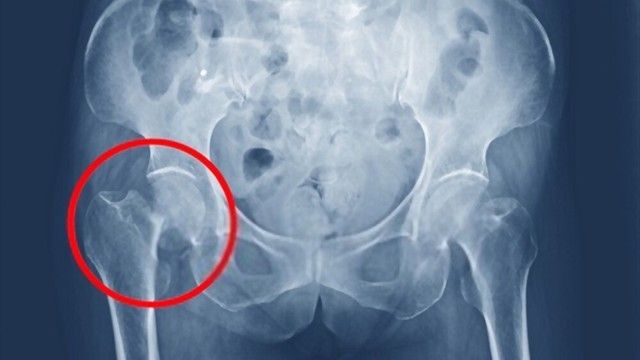

Hoại tử khớp háng đang ngày càng trở nên phổ biến và có xu hướng ảnh hưởng đến những người trẻ tuổi. Đây là một bệnh lý nghiêm trọng với khả năng gây tàn tật cho người mắc, tuy nhiên lại phát triển âm thầm và dễ bị nhầm lẫn với các bệnh lý khác. Vậy nguyên nhân, triệu chứng và cách chẩn đoán hoại tử khớp háng là gì? Để giải đáp thắc mắc mời bạn đọc cùng tham khảo bài viết dưới đây.